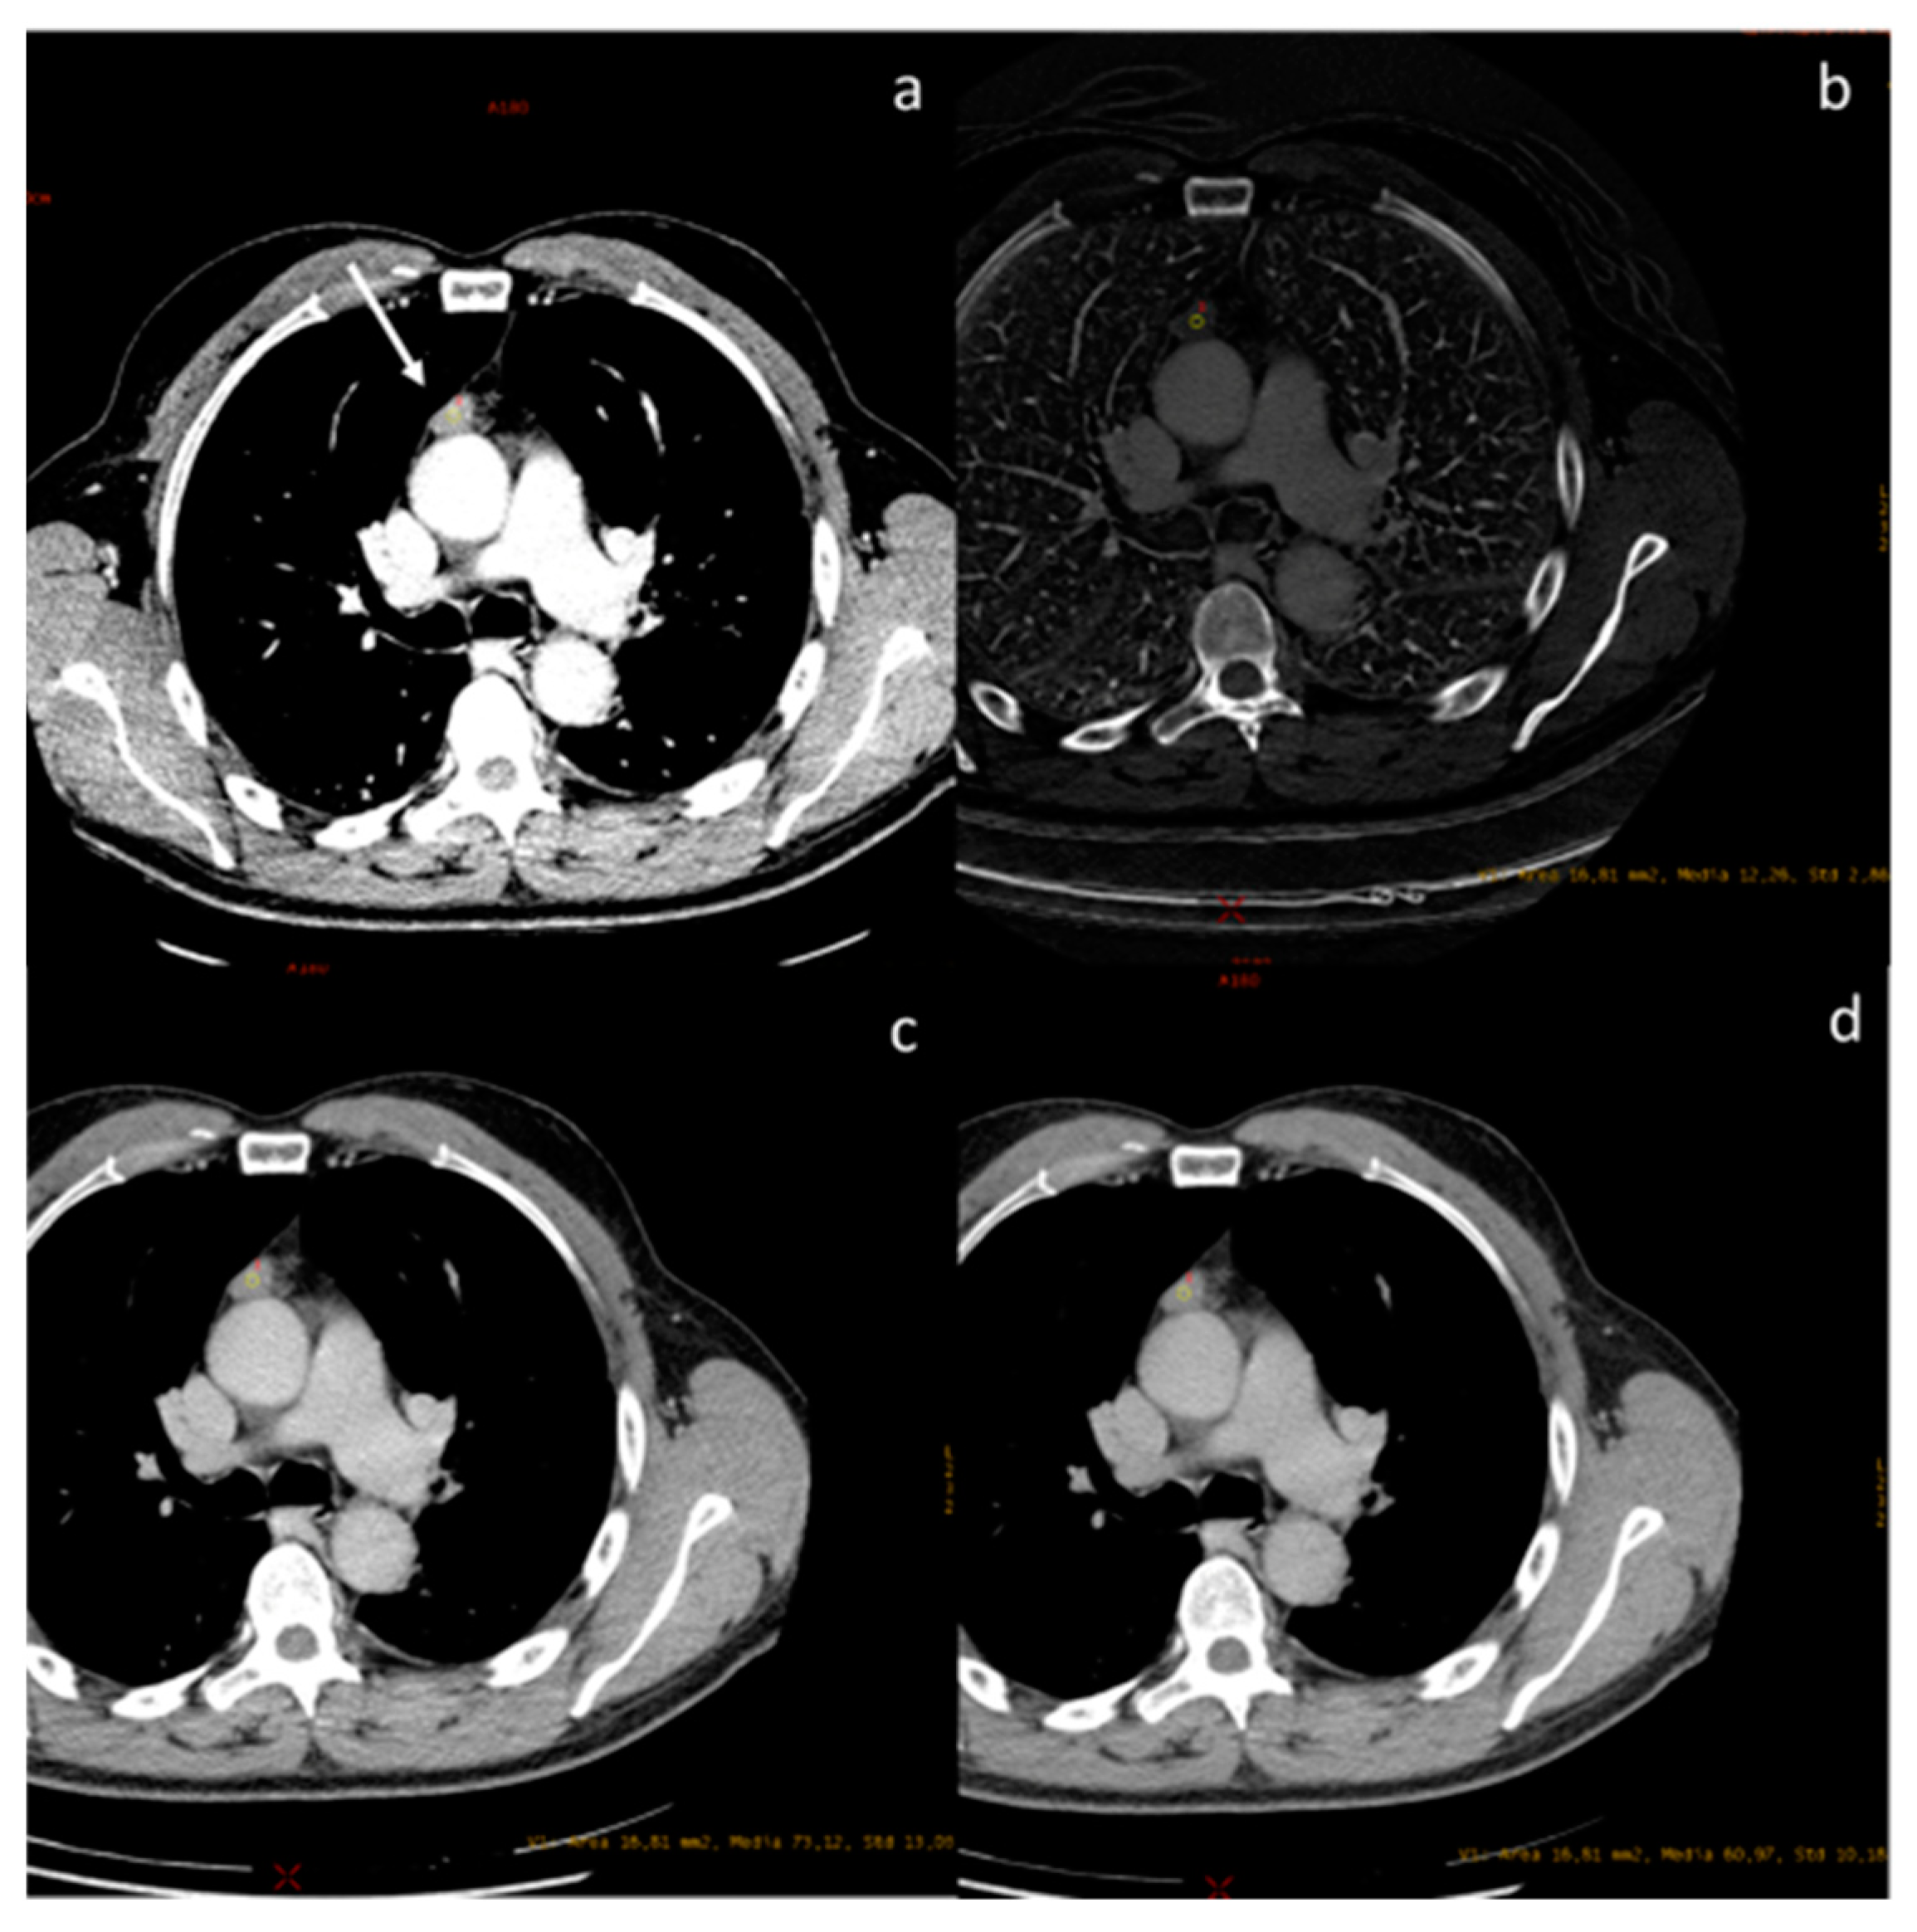

- Volterrani, L.; Gentili, F.; Fausto, A.; Pelini, V.; Megha, T.; Sardanelli, F.; Mazzei, M.A. Dual-Energy CT for Locoregional Staging of Breast Cancer: Preliminary Results. Am. J. Roentgenol. 2020, 214, 707–714. [Google Scholar] [CrossRef] [PubMed]

| Volterrani et al. [57] Retrospective study | Italy | To demonstrate the feasibility of DECT for locoregional staging of breast cancer and differentiation of tumor histotypes | 31 | Discovery CT 750 HD, GE Healthcare No C.I. | DECT is feasible and seems to be a reliable tool for locoregional staging of breast cancer. |